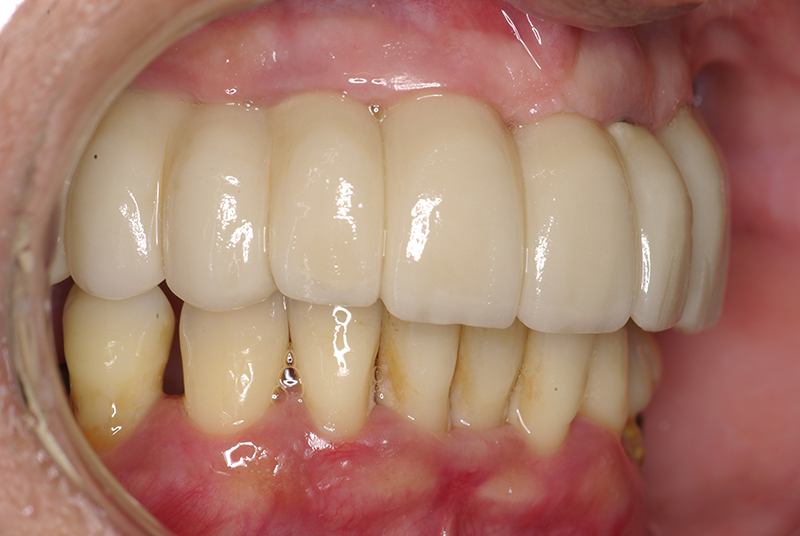

Na Clínica Pontes Odontologia, somos referência em implantes dentários em Fortaleza, oferecendo tratamentos de alta qualidade e tecnologia de ponta. Os implantes dentários são estruturas de titânio posicionadas cirurgicamente no osso maxilar ou mandibular para substituir as raízes dos dentes ausentes. Essa técnica permite a fixação de próteses personalizadas, restaurando a função mastigatória, a estética e a autoestima dos nossos pacientes.

Utilizamos a tecnologia CAD CAM, um sistema avançado que possibilita a confecção precisa das próteses dentárias diretamente sobre os implantes. Esse método inovador garante um ajuste perfeito, um resultado estético superior e proporciona muito mais conforto e durabilidade. Com o CAD CAM, nossos pacientes contam com um processo mais rápido e previsível para alcançar o sorriso desejado.